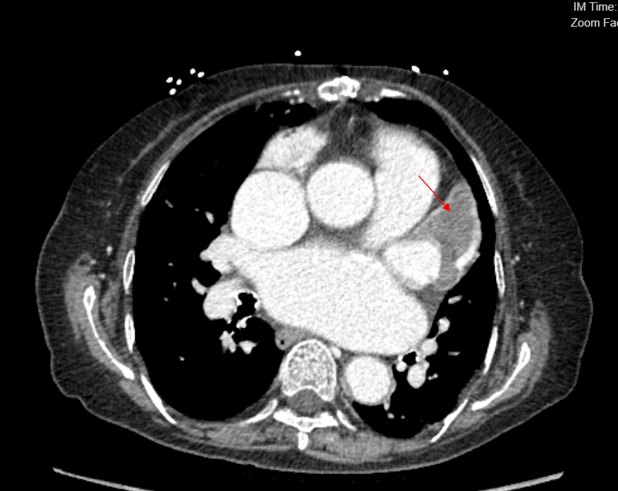

We performed transseptal puncture using Versacross wire (Baylis Medical) and Baylis catheter, followed by septostomy using a 14 mm Armada balloon (Abbott) (Figure 3). We then advanced the AlphaVac system (Angiodynamics) to the left atrial and directed the tip of the funnel towards the thrombus (Figure 4), which was successfully removed after multiple runs of aspiration using the AlphaVac system. (Figure 5A, B). The system was then removed, and the femoral venous access was closed using Perclose (Abbott). The patient was transferred to the cardiothoracic intensive care unit for further monitoring. Unfortunately, after transfer, a stroke occurred in the patient’s right middle cerebral artery. Her goals of care were discussed with the family, and she was transitioned to comfort care. She died 3 days post-procedure.